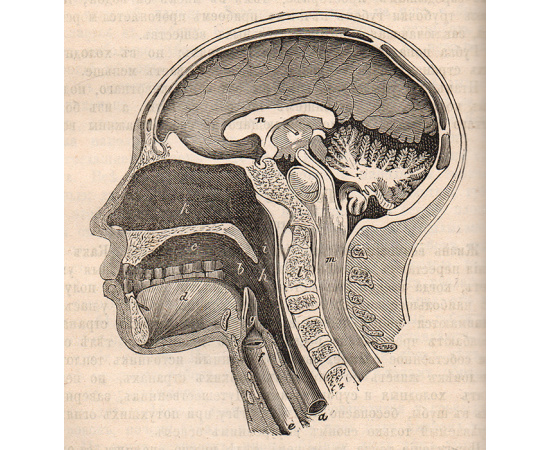

В книге также присутствуют иллюстрации и фотографии, которые визуально дополняют тексты и помогают детям лучше визуализировать представленные материалы. Это помогает им увидеть реальные образцы и примеры из окружающего мира и более полно воспринять их.

В книге также присутствуют иллюстрации и фотографии, которые визуально дополняют тексты и помогают детям лучше визуализировать представленные материалы. Это помогает им увидеть реальные образцы и примеры из окружающего мира и более полно воспринять их.